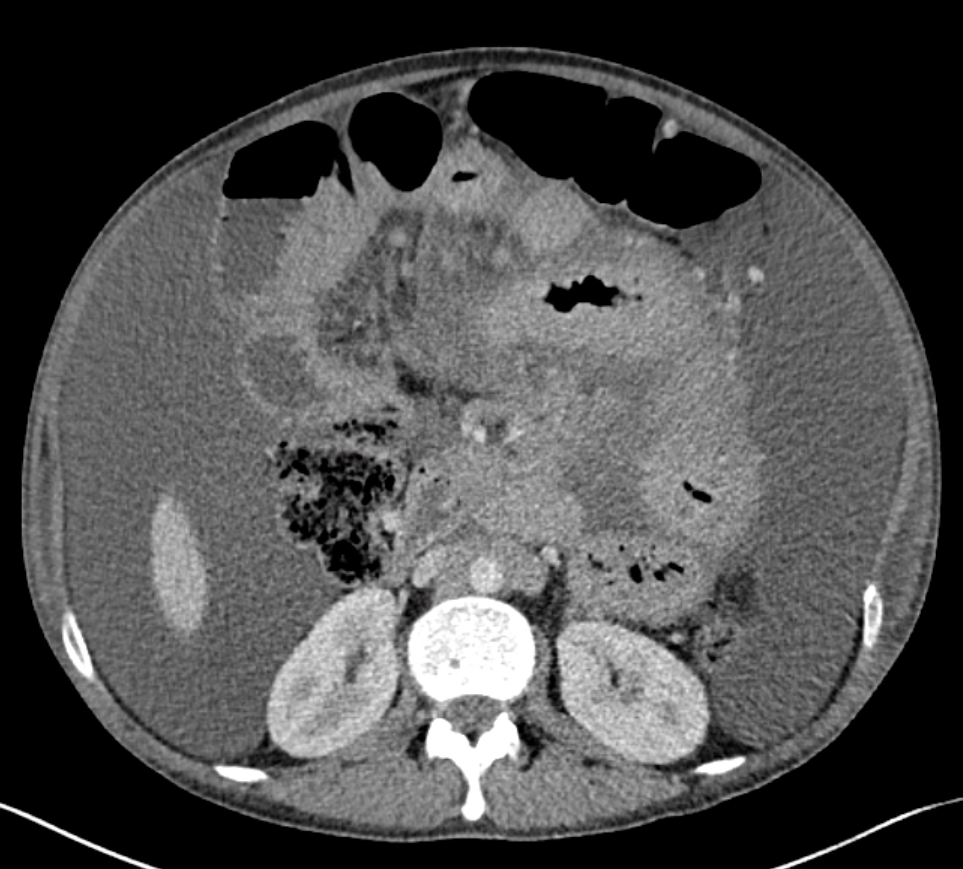

Case Presentation: A 29-year-old male with a history of HIV/AIDs on antiretroviral therapy (ART), prior cryptococcal meningitis, and mycobacterium avium complex (MAC) colitis presented to the ED with a three-week history of worsening abdominal pain and distension. His MAC colitis was diagnosed earlier that year and treated with clarithromycin and ethambutol. However, the ethambutol was discontinued due to concern for optic neuritis, so he was switched to macrolide monotherapy for three months. He had normal vital signs and physical exam showed abdominal distension with a positive fluid shift and diffuse tenderness to palpation without guarding or rebound tenderness. Labs were notable for mild elevation of alkaline phosphatase (192 U/L), anemia (Hgb 10.6 g/dl) and thrombocytosis (607 10³/µL). CT abdomen demonstrated abnormal soft tissue/nodularity along the root of the small bowel mesentery and retroperitoneal lymphadenopathy with ascites and mesenteric edema. He underwent paracentesis which revealed chylous ascites and cultures were positive for MAC. The patient endorsed mild relief of his abdominal symptoms after the paracentesis, but his abdomen became noticeably distended in the days following. After negative ophthalmologic workup, ethambutol was resumed along with azithromycin and rifabutin. He required repeat outpatient paracentesis due to fluid re-accumulation.

Conclusions: Hospitalists should consider MAC colitis with chylous ascites in patients with HIV/AIDs on ART with low CD4 count. Patients may present with nonspecific symptoms and lab abnormalities of anemia, elevated alkaline phosphatase and lactate dehydrogenase. CT is useful to evaluate for lymphatic obstruction secondary to MAC infection. Patients with MAC infections should be treated promptly with a macrolide plus ethambutol. Should ethambutol be discontinued for ophthalmologic concerns, prompt replacement with an appropriate alternative is indicated.